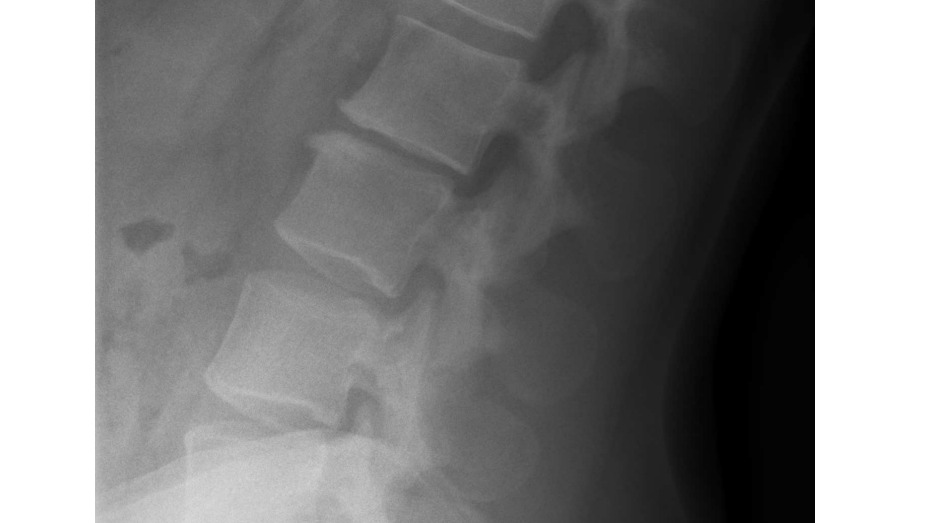

Hello my name is Krista Bain When I was a teenager I was in a incident where I came of a sprinting horse. The horse flwe me in the air and I landed crash down on my back with a 'crunch' sound in my spine. I felt tingling in my legs and adrenaline kicking in. I was so afraid. I was in shock unable to get up or move. I waited what felt to hours pass by and managed to slowly grasp myself to a stand. When I arrived back to to the horse stable I told the people there what happened. They comforted me and let me call my caregiver( I will not make the person to there discression)They knew the horse I was riding was not tame as did I but I regretfully chose to ride this horse regardless.I was instructed to go to hospital and tell my caregiver to take me there.The drive was around 45 mins from home and longer to the hospital Because I had come off horses many many times in the past my caregiver decided to make the decision not to take me to the hospital to be examined. I was in alot of pain stopped riding and took weeks off school. Because of this eventually my caregiver took me to a medical centre but when I spoke she downplayed what I said out of embarrassment of not providing my care at the time and I left that appointment deviated and without any Acc claim or examination. I have finally received a doctor after many attempts for x-rays that went unnoticed be ause I didn't receive a claim to begin with. The x-ray shows L2 &L1 fractures that have healed and a concaved scelrosis of the lower spine. The pain has only gotten worse over the years and without nerve pain killers 5 times per day I'm in absolute agony. I am afraid to take these pills for the rest of my life. I am unable to receive any help for surgery from Acc because this is a past incident. I have not been able to keep any work because my pain get heightened with any form of physical work. I am afraid of ending up in a wheelchair when I am older and having to take nerve painkillers for the rest of my life. I have a six year old son and I really cannot bare the thought of the future going downhill like this. I am afraid of being stick for the rest of my life due to the neglect of my caregiver. I have big dream to accomplish I have a great voice, I was a champion at netball and I love animals horseriding and travel. I feel down and out and the pain is closing off my ability to speak up and to get out and do things I would usually enjoy. I want to be a great role model for my son and work a great deal and provide the life for myself and my son so he can have a good future as well. I need to raise $21,000 for a lower spinal infusion surgery to be able to get this done. I would greatly appreciate any help and I thankyou ? Krista